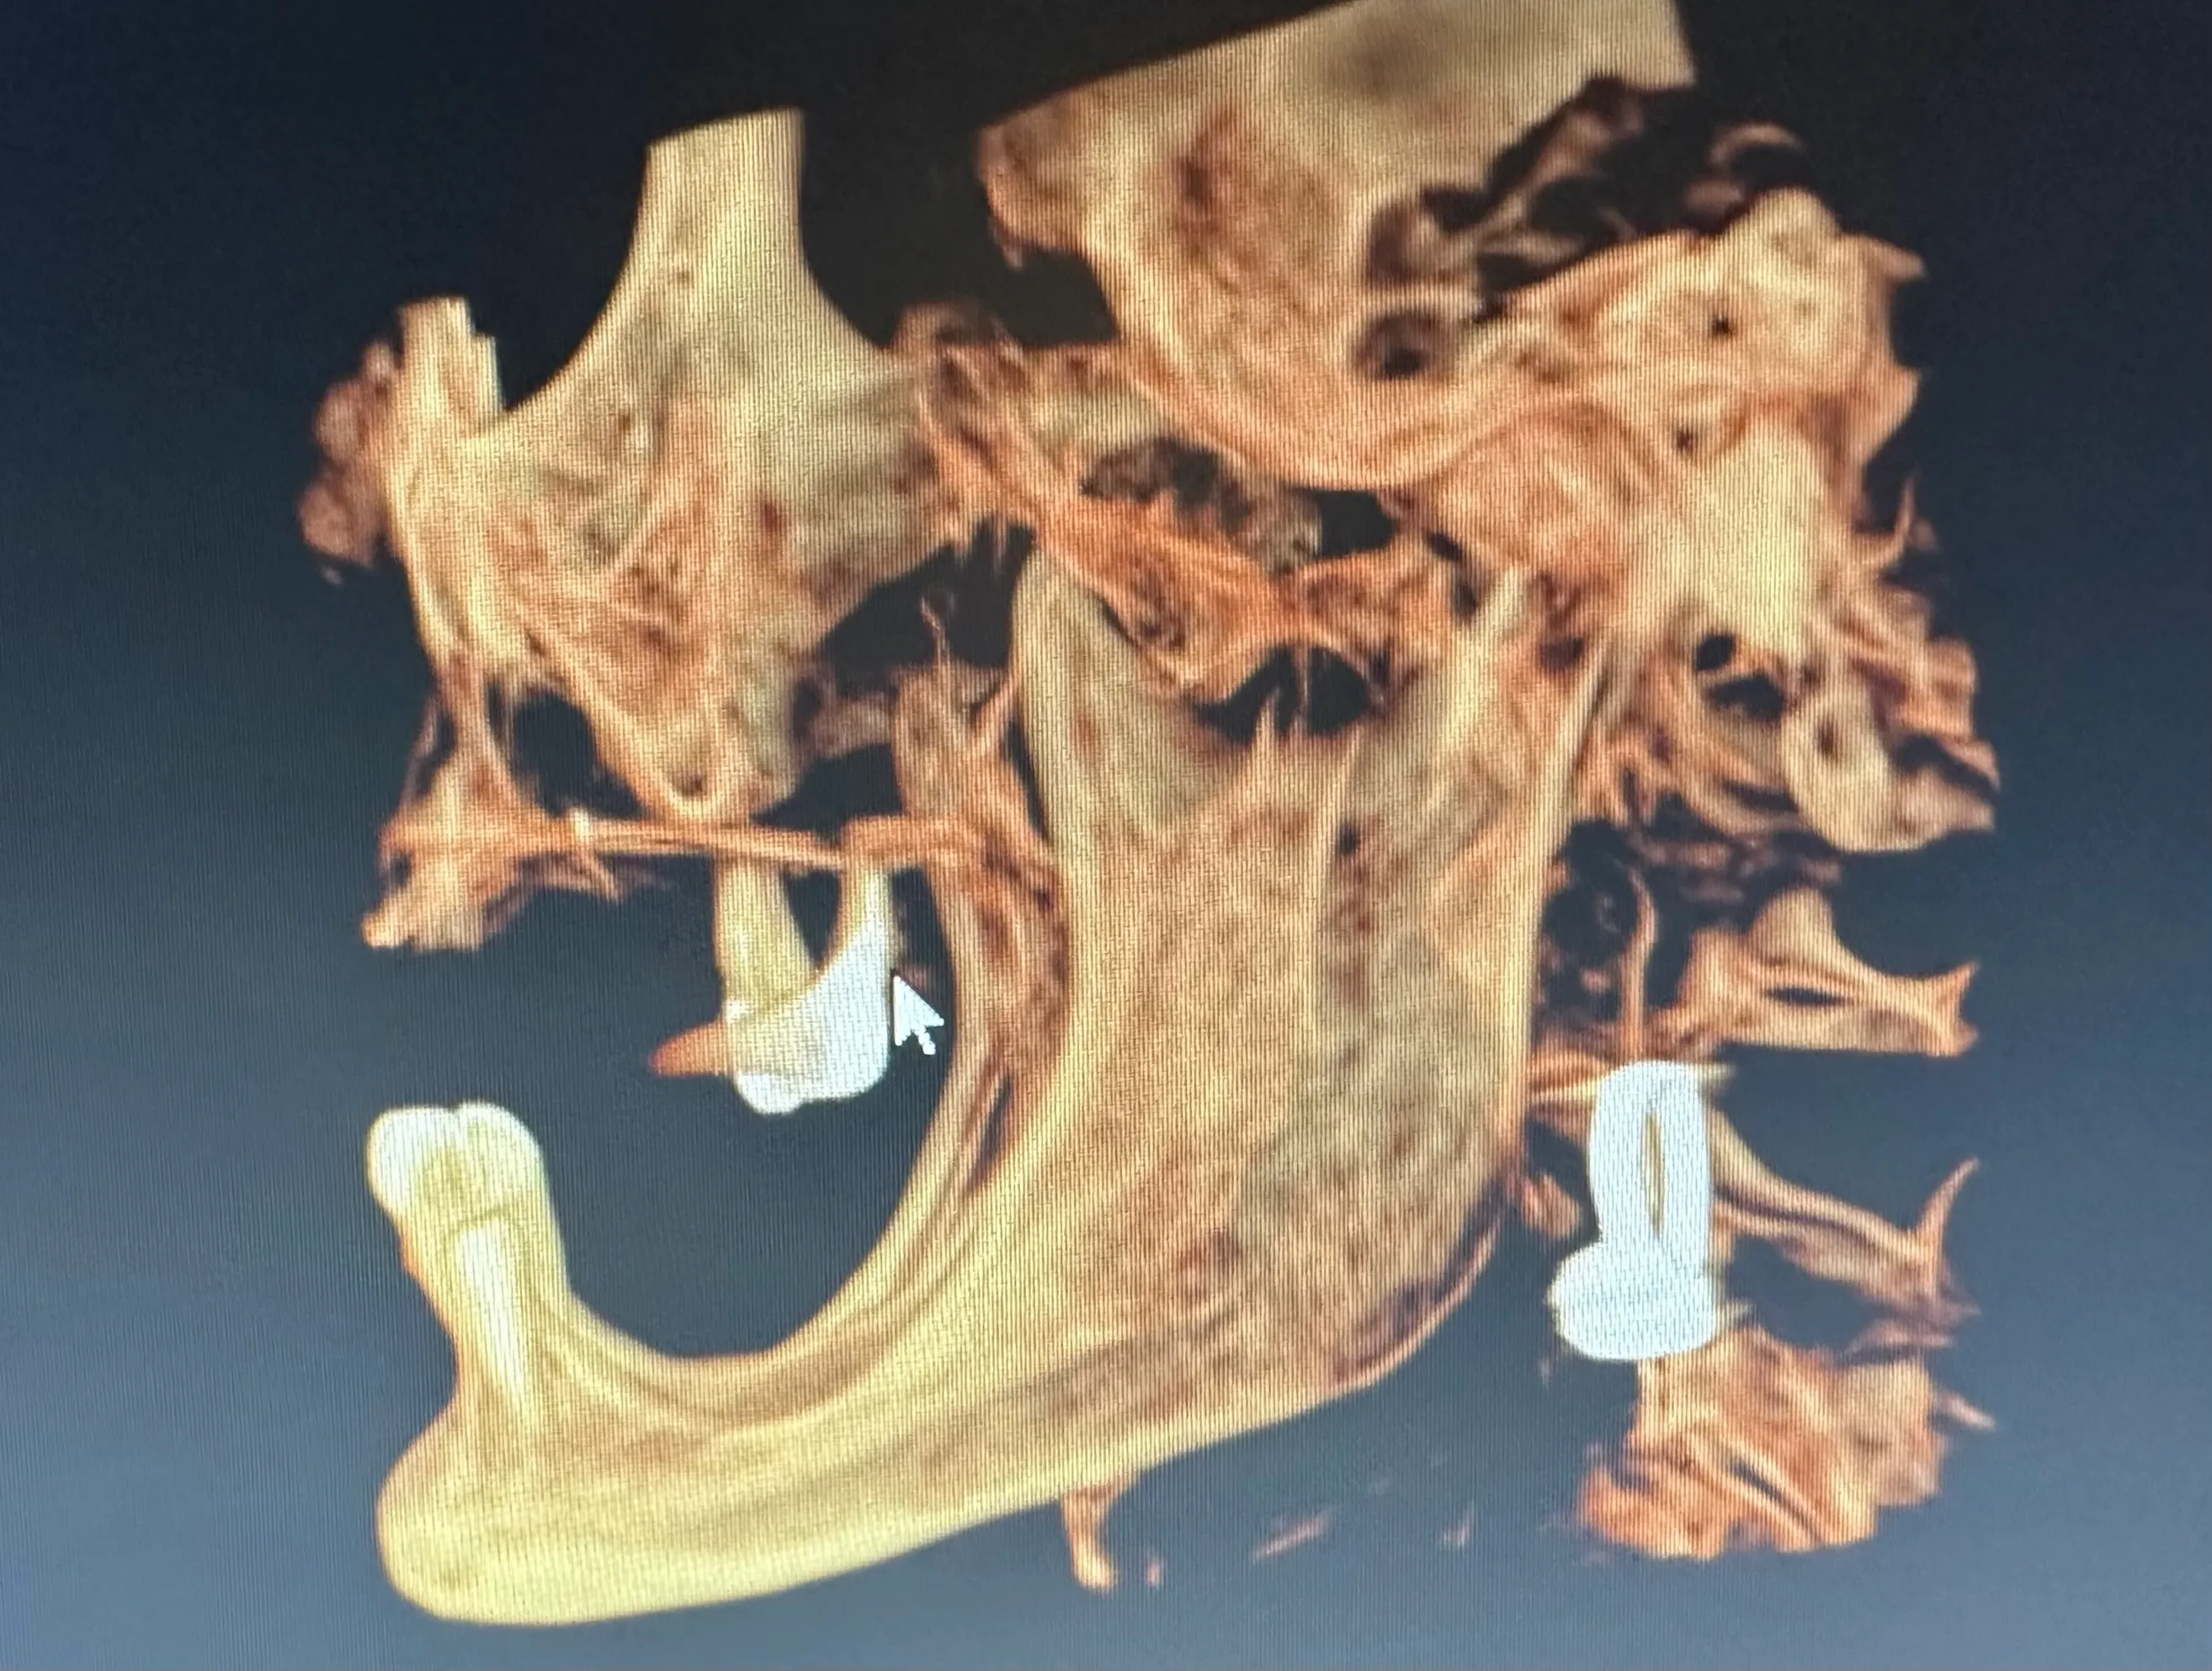

X-ray image of a jaw with dental implants and surgical plates, highlighting the alignment of teeth and orthopedic hardware.

Some patients need only one or two dental implants, while others are completely edentulous (missing all teeth). As with other well-known implant-supported denture options, zygoma implants can support a full arch of prosthetic teeth on just four screws without bone grafting.

Normally, implants are placed in the maxilla to replace missing teeth in the upper jaw. However, some patients have such severe bone loss that there isn’t enough to place an implant safely. In this case, longer implant screws can be used to reach the cheekbones, which are used as an anchor instead.

Zygomatic dental implants are sometimes called “rescue implants” because they can help patients achieve a fully functional bite and aesthetically pleasing smile when bone grafting isn’t possible.

Without regular stimulation from chewing and biting, jawbone loss (resorption) occurs. We frequently see significant bone loss in patients who have been using dentures for many years. Unfortunately, patients with maxilla resorption are often told that there is no hope for bone grafting or dental implants. However, this is not always the case.